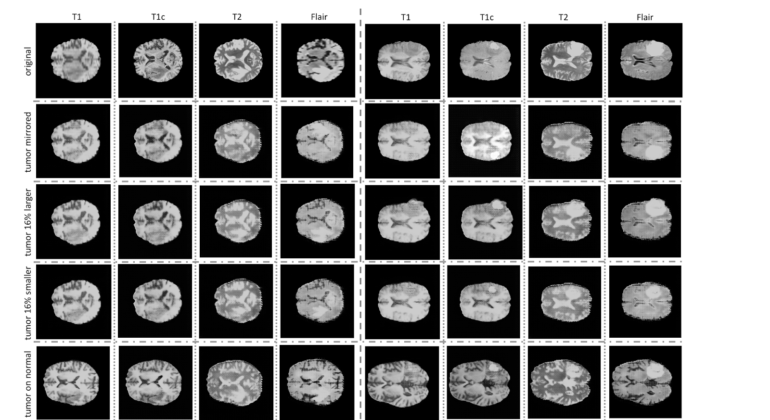

Generando escaneres cerebrales con IA

Una de las grandes limitaciones que tiene el aprendizaje automático es la gran cantidad de datos que necesita para entrenar un algoritmo; datos que han sido previamente etiquetados. La precisión del algoritmo dependerá directamente del tamaño del set de datos. Investigadores de Nvidia y varios …